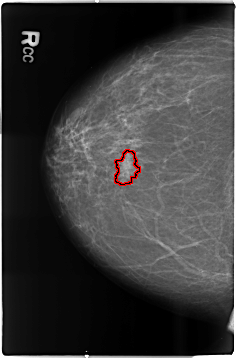

FILE: B_3506_1.RIGHT_CC.OVERLAY

TOTAL_ABNORMALITIES 1

ABNORMALITY 1

LESION_TYPE MASS SHAPE FOCAL_ASYMMETRIC_DENSITY MARGINS ILL_DEFINED

ASSESSMENT 4

SUBTLETY 3

PATHOLOGY MALIGNANT

TOTAL_OUTLINES 1

BOUNDARY

B_3506_1.RIGHT_CC

RIGHT_CC LINES 4648 PIXELS_PER_LINE 3056 BITS_PER_PIXEL 12 RESOLUTION 50 OVERLAY